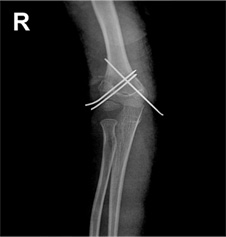

과상부 골절 수술 후

x-ray 사진